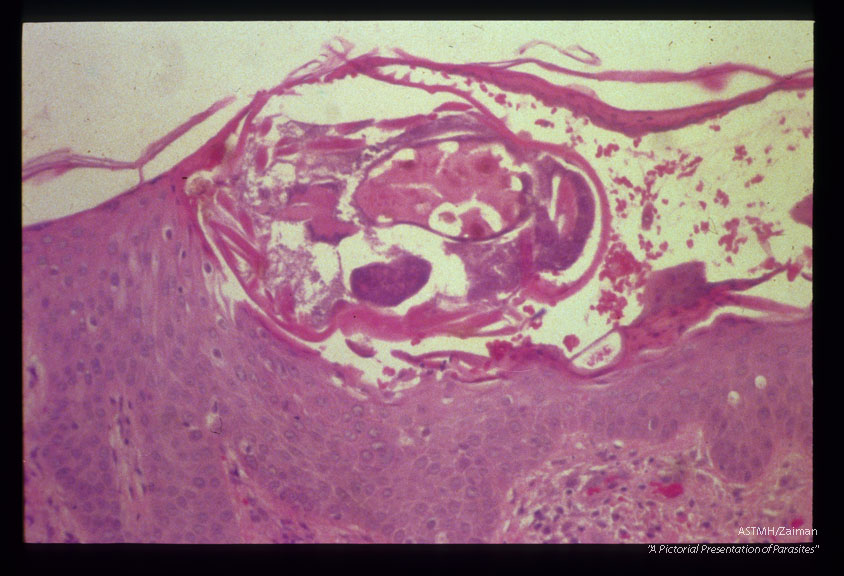

Mite in skin.

Sacroptes scabiei

Description: Mite in skin.